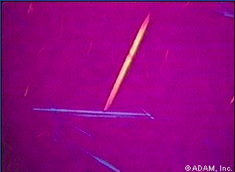

* Cytology – joint fluid shows needle-shaped crystals

* Histology – amorphous eosinophilic debris (giant cells), will not see crystals, another form of crystal arthropathy that can look similar = pyrophosphate arthropathy

Cytology pseudogout?

Crystals are bigger, coarser and more rhomboid in shape (in contrast to urate crystals)